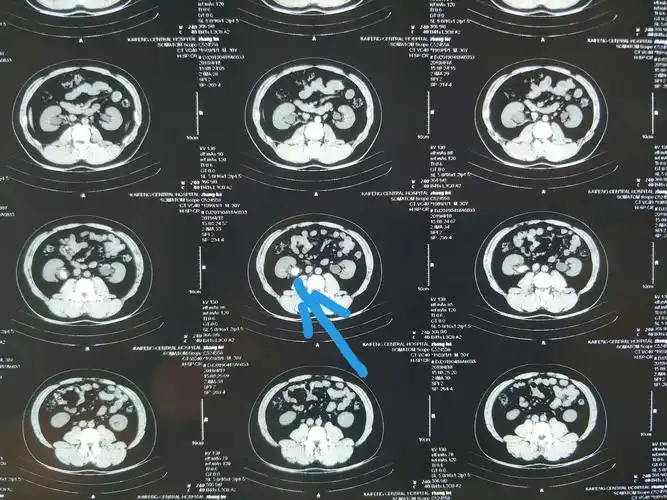

门静脉轻度扩张.